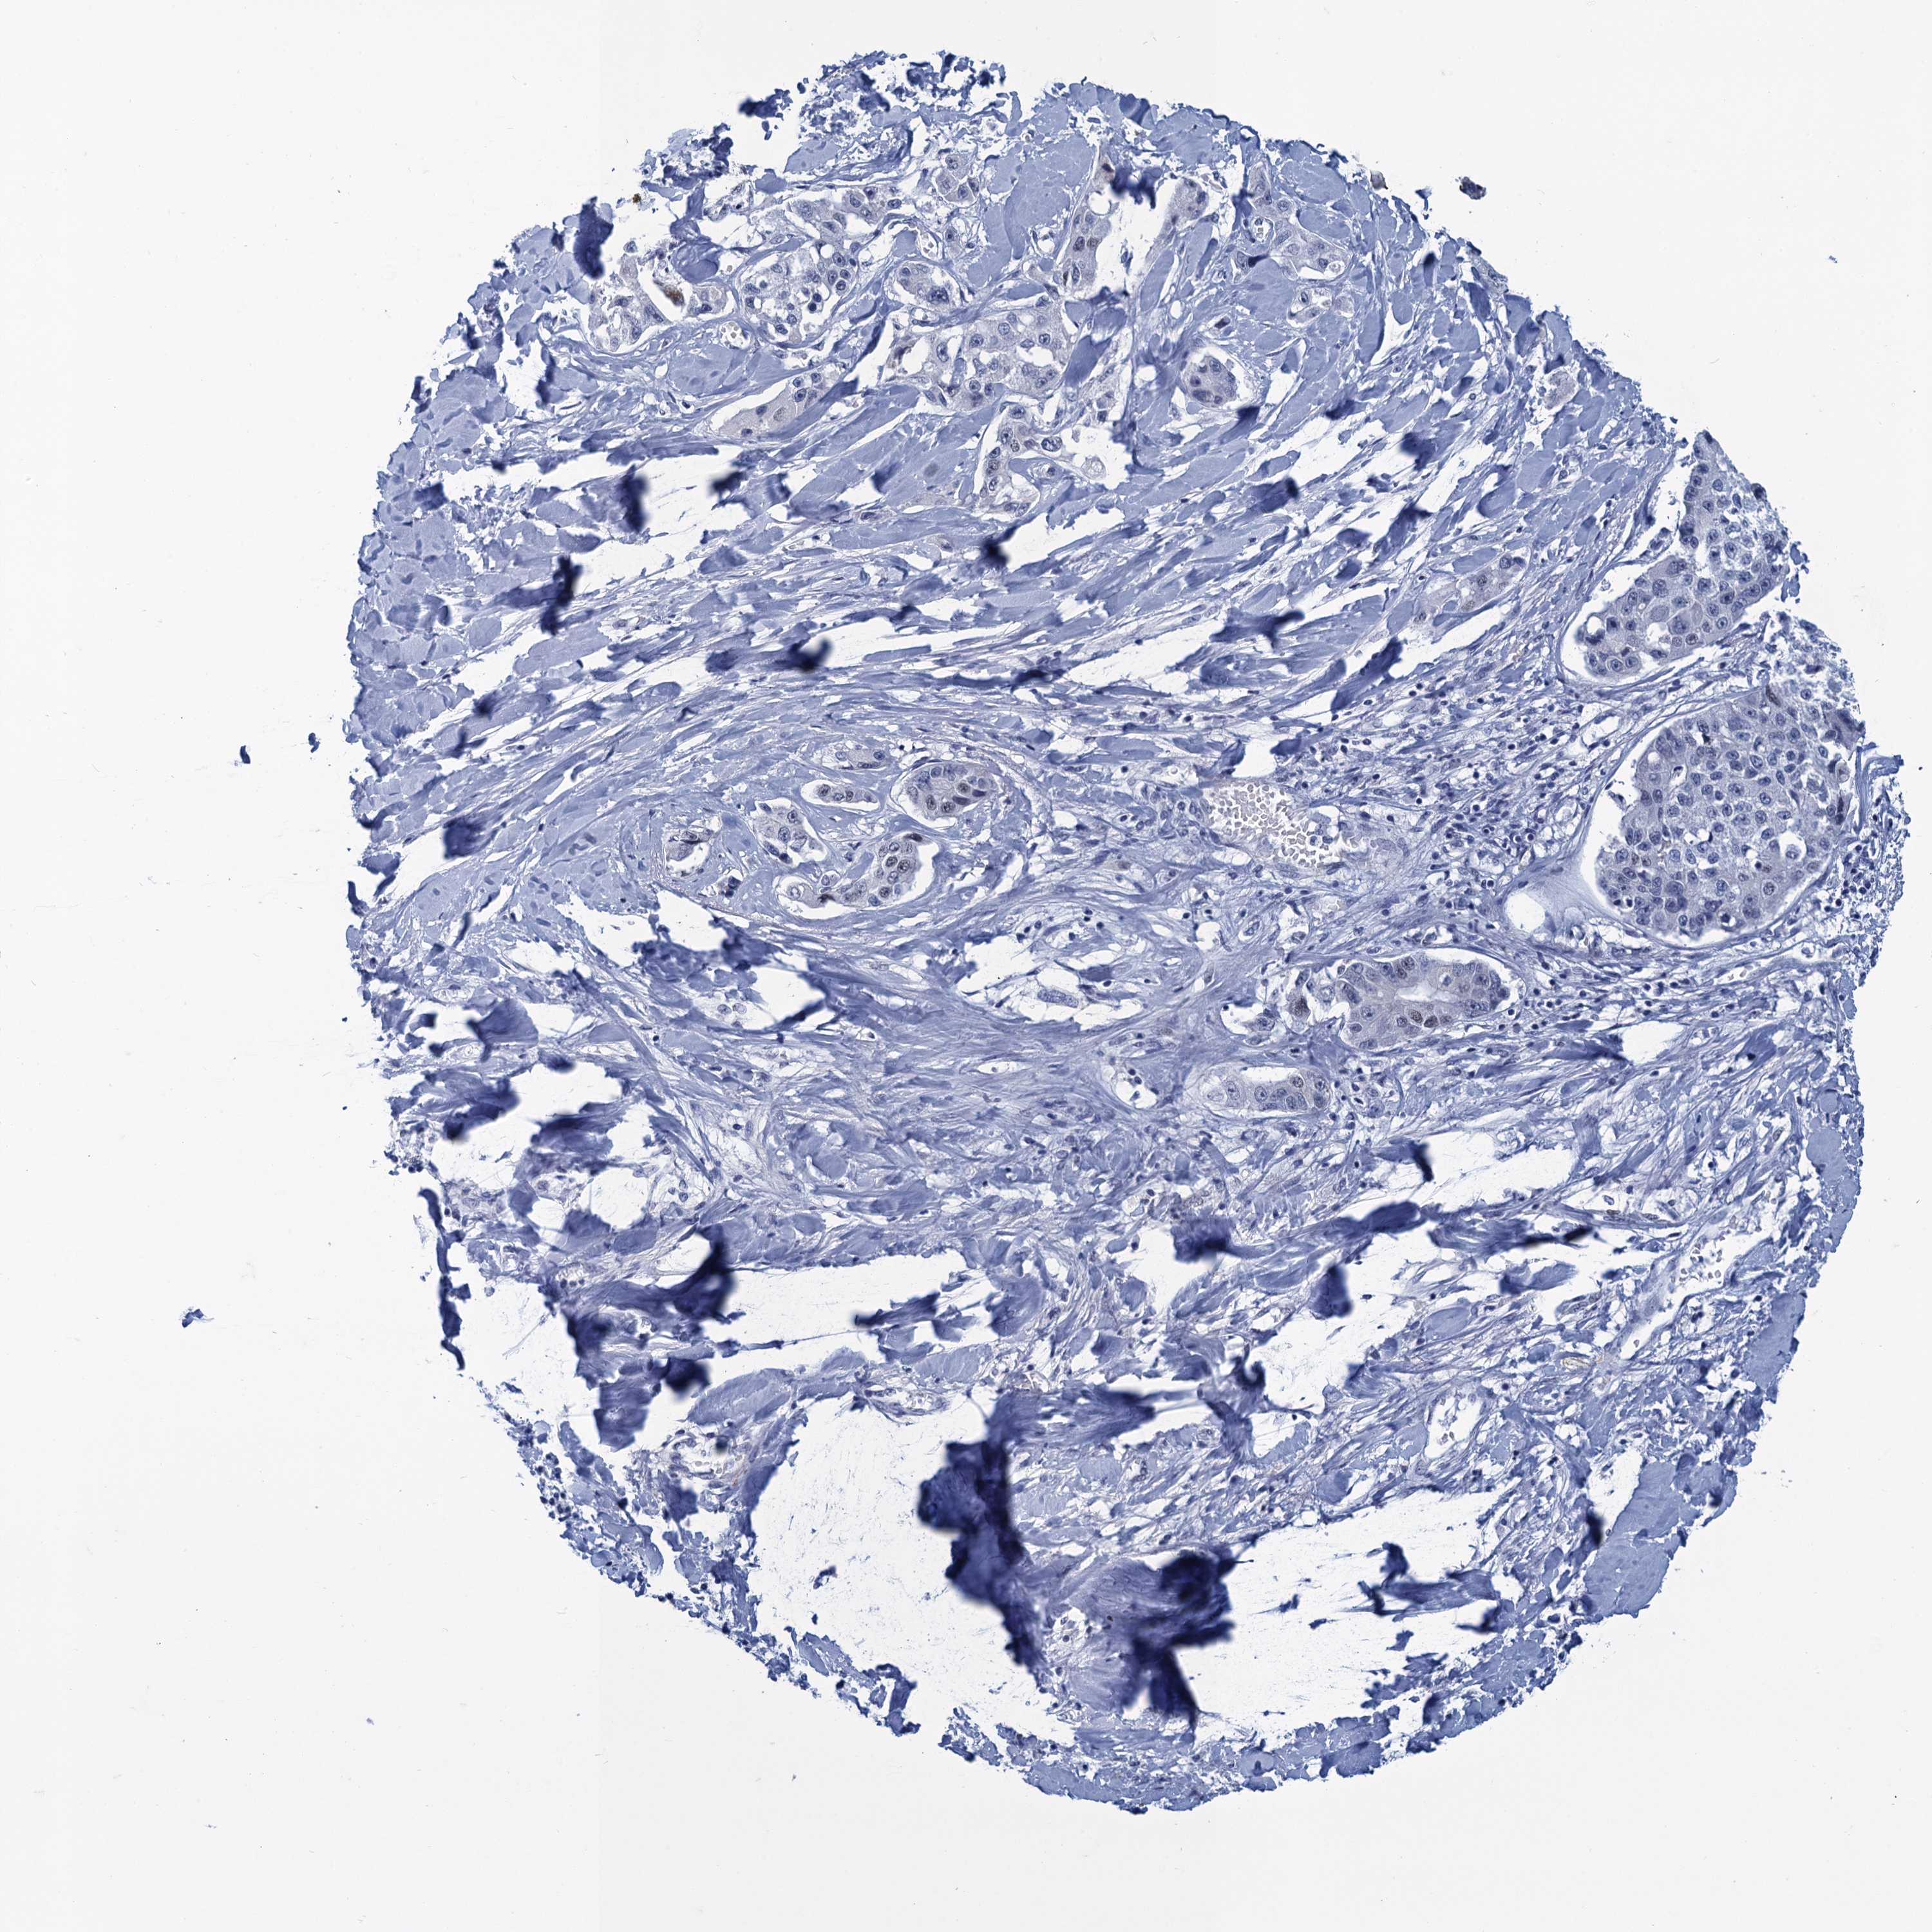

LIVER CANCER - Protein expressioni

A mouse-over function shows sample information and annotation data. Click on an image to view it in a full screen mode. Samples can be filtered based on level of antibody staining by selecting one or several of the following categories: high, medium, low and not detected. The assay and annotation is described here.

Note that samples used for immunohistochemistry by the Human Protein Atlas do not correspond to samples in the TCGA dataset.

Antibody stainingi

Antibody staining in the annotated cell types in the current human tissue is reported as not detected, low, medium, or high, based on conventional immunohistochemistry profiling in selected tissues. This score is based on the combination of the staining intensity and fraction of stained cells.

Each image is clickable and will lead to virtual microscopy that enables deeper exploration of all samples and also displays staining intensity scores, fraction scores and subcellular localization as well as patient and tissue information for each sample.

Antibody HPA041216

Staining

High

Medium

Low

Not detected

Intensity

Strong

Moderate

Weak

Negative

Quantity

>75%

75%-25%

<25%

None

Location

Nuclear

Cytoplasmic/membranous

Cytoplasmic/membranous,nuclear

Cholangiocarcinoma

Carcinoma, Hepatocellular, NOS